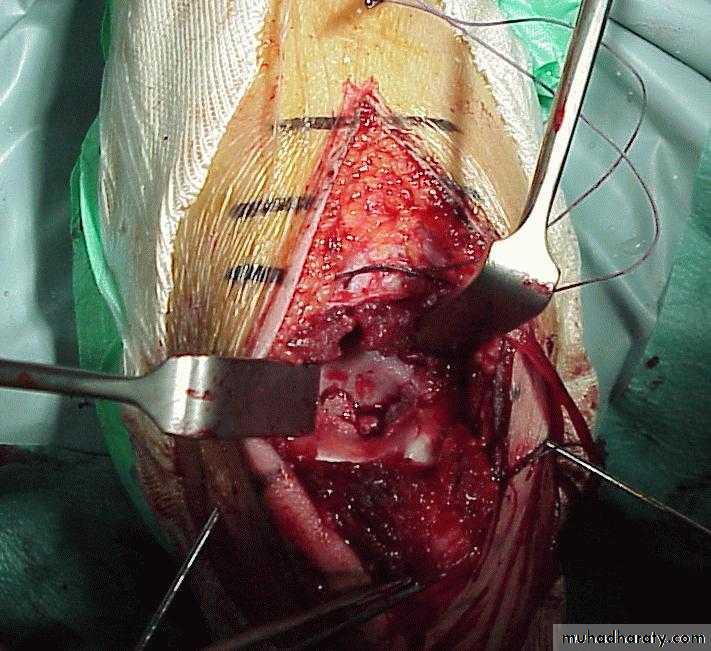

What is the operative approach ?

It involves an anteromedial incision.

Ulnar NerveAnterior N.V. Bundle

Medial

spike

One needs to be able to see the: